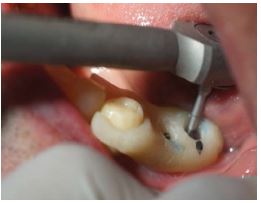

Se procedió a la transferencia de los pilares en el maxilar superior con cubeta abierta y ferulización de transfer (Figura 4), y a la transferencia de la plataforma de los implantes en el maxilar inferior.